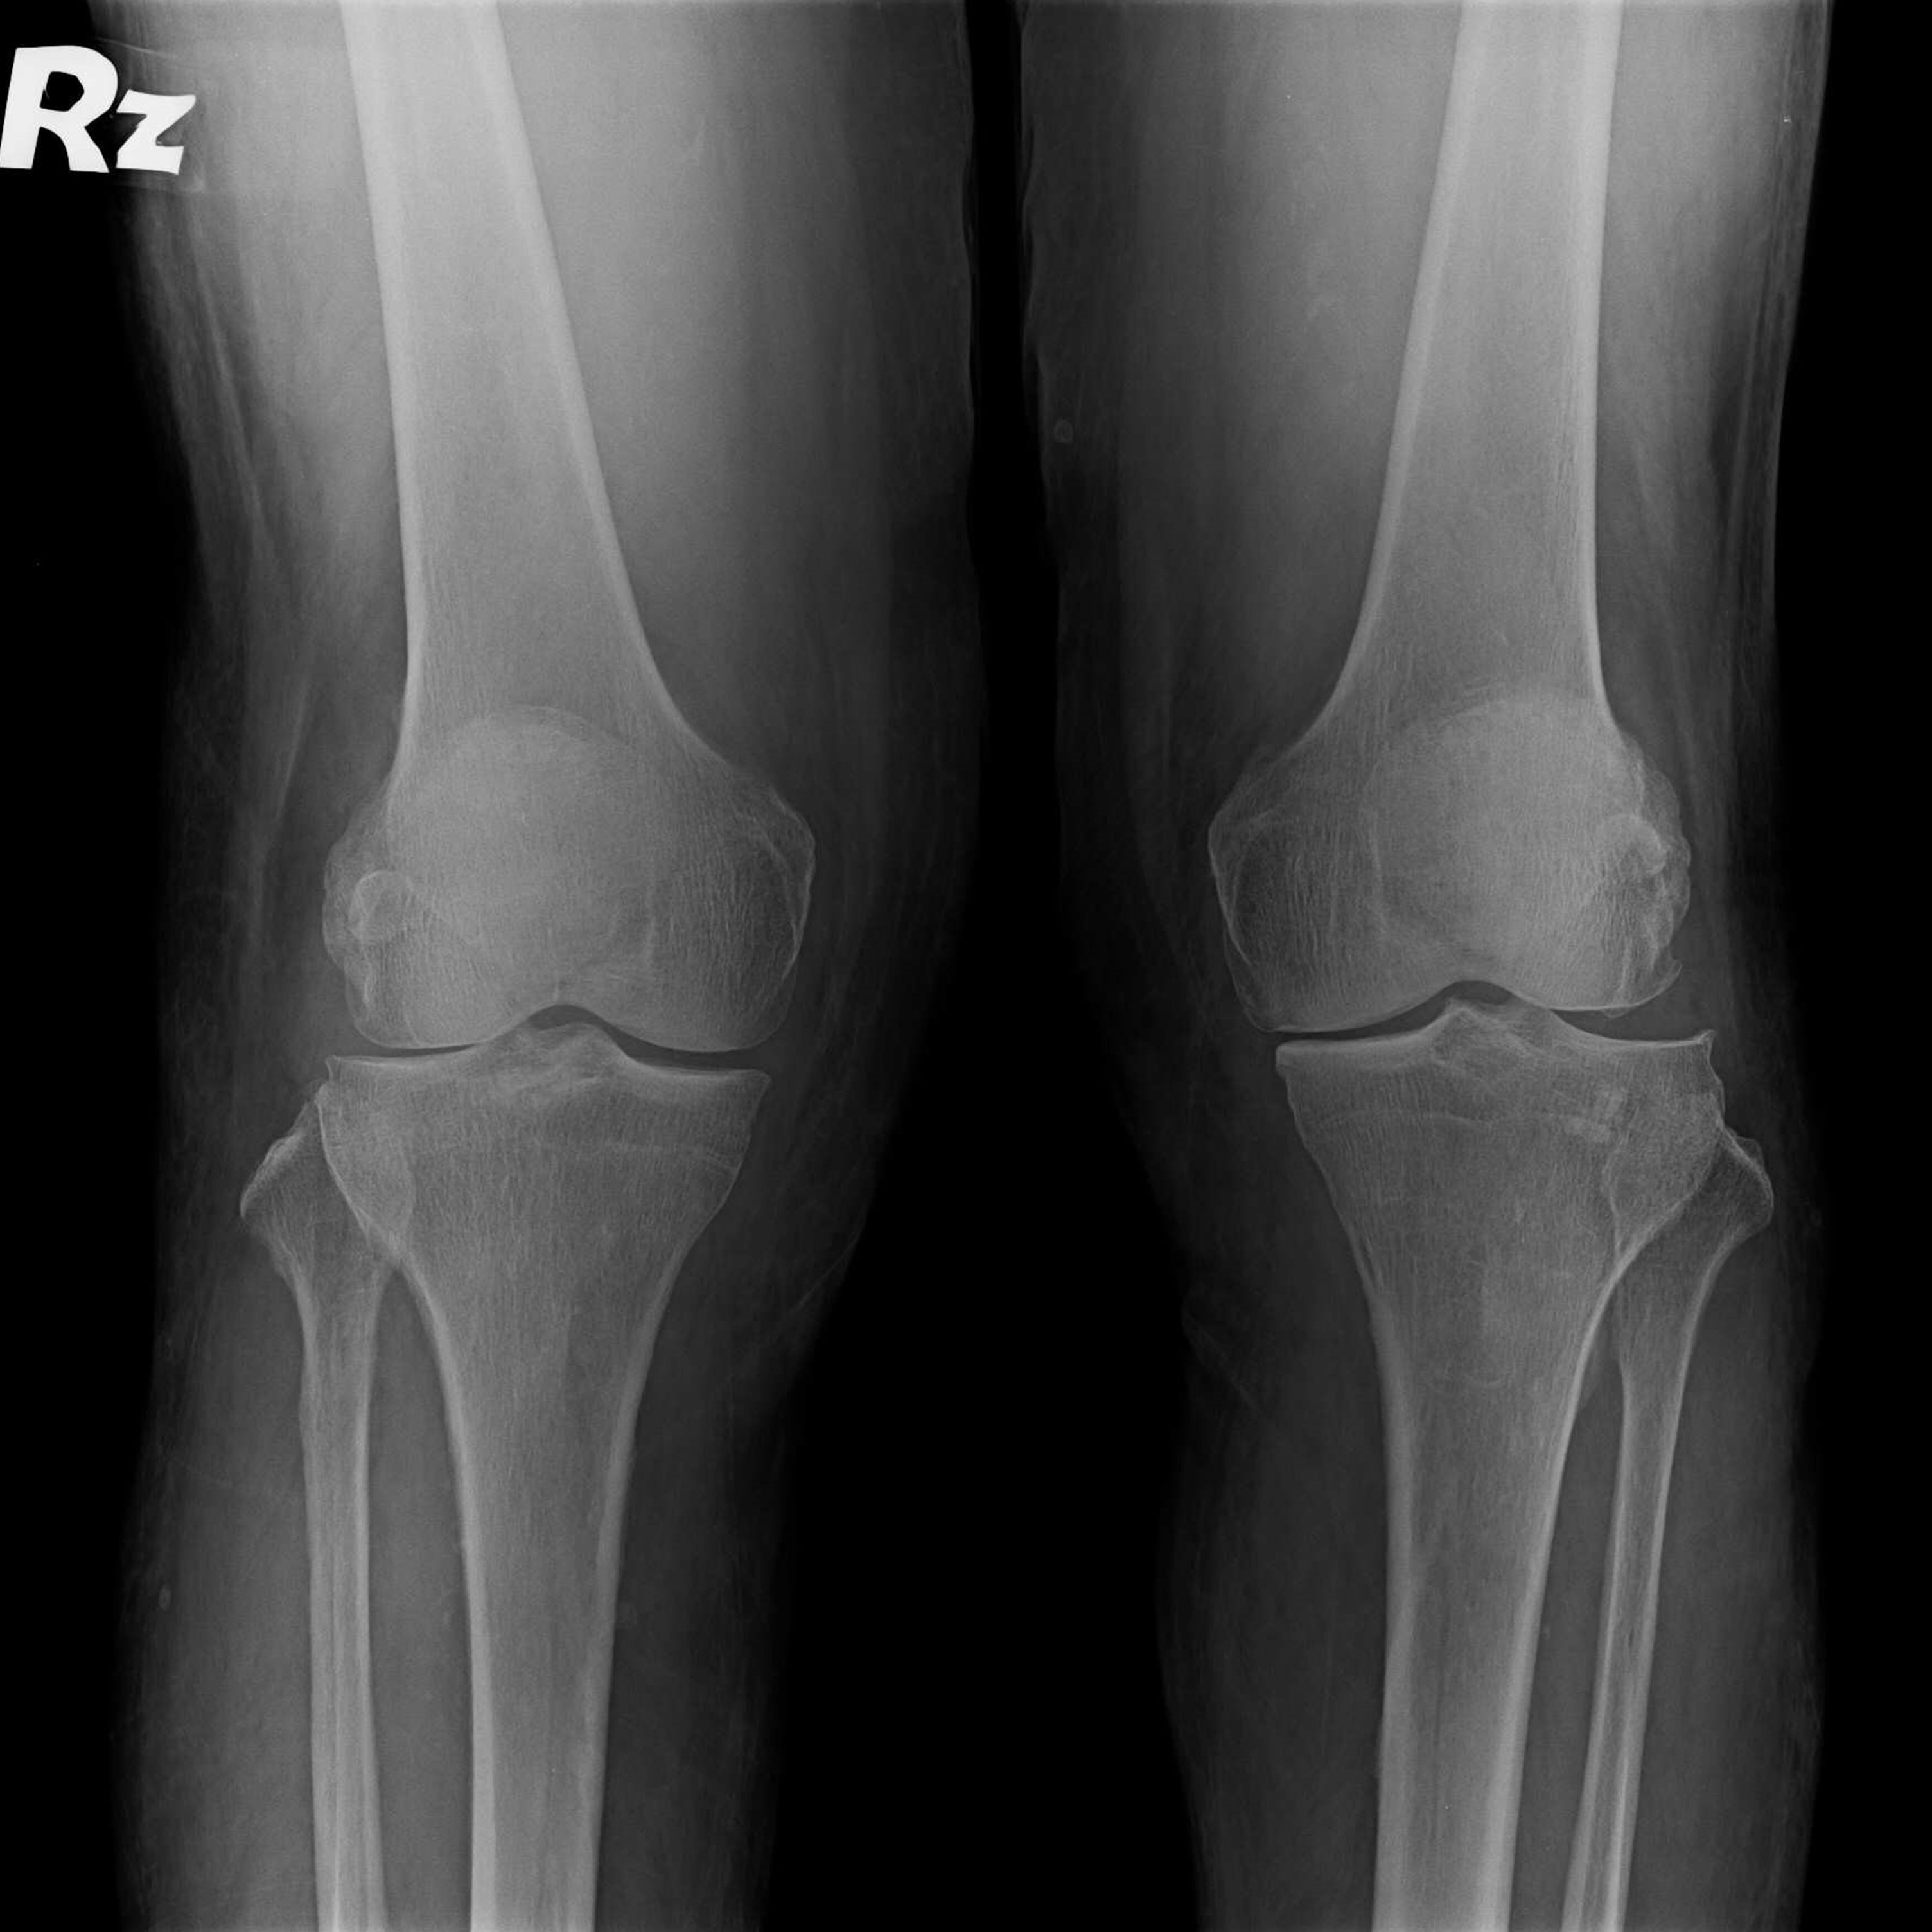

傳統全膝關節置換 首頁 案例分享 膝關節手術 傳統全膝關節置換 江女士 61歲 術前 術後 劉先生 83歲 術前 術後 70歲 柯先生 術前 術後 75歲 黃女士 術前 術後 77歲 羅女士 術前 術後